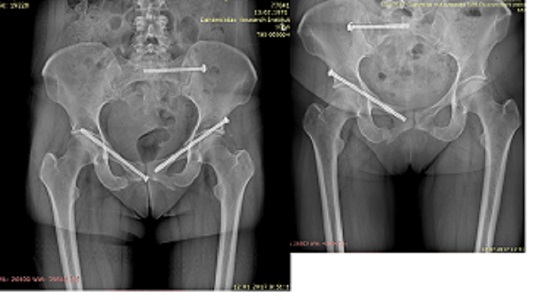

Доброго времени суток! Сочетанная травма в результате ДТП от 15.12.16., закрытая травма таза с ротационно-нестабильным повреждением тазового кольца, переломы обеих лонных, седалищных костей, трансфораминальный перелом боковой массы крестца слева.

Остеосинтез 3 винтами. Правый винт удален через 3 месяца. По поводу остальных есть 2 мнения: удалять или оставить, помогите принять правильное решение.

46 лет, врач педиатр, производственная травма при выезде к пациенту, пассажир. На КТ от 24.07.17. полной консолидации в крестце ниже винта нет. Извиняюсь за качество снимков, первый от 12.01.17., второй от 18.07.17. С уважением.